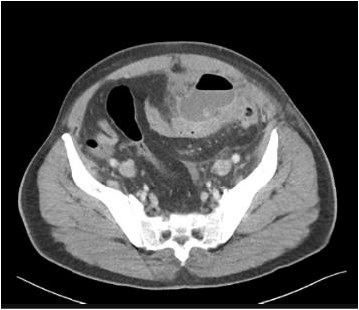

Paciente, 58 anos, chega ao pronto atendimento com história de dor em fossa ilíaca esquerda, que piorou progressivamente nas últimas 48 horas, sem febre. O exame físico mostrou abdome pouco distendido, doloroso à palpação difusa, dor à palpação mais localizada em fossa ilíaca esquerda, onde o sinal de Blumberg apresenta-se positivo.

O hemograma mostra contagem de leucócitos de 13.500/mm3 com 867 bastões, e a dosagem do PCR foi de 23 mg%. Foi solicitada a TC de abdome mostrada abaixo.